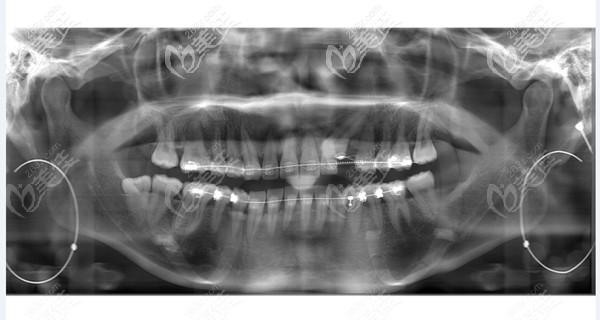

所以袁珂醫(yī)生讓她先拍個(gè)片子,看下具體口腔里的牙齒是啥樣的,沒想到具體的結(jié)果是醬紫的。

果不其然確實(shí)是少了一顆牙,但是我們也可以很清晰的看到漏洞地方里面還有一顆牙,只是這個(gè)牙是歪的。

經(jīng)過醫(yī)生分析講解后才明白,原來是因?yàn)樾r(shí)候的乳牙沒有掉,所以后來的尖牙沒有“萌出”而導(dǎo)致的。

袁珂醫(yī)生給出方案是“正畸+萌牙”,就是把里面隱藏的牙齒糾正,通過牙齒矯正的方式來讓它來彌補(bǔ)空牙的位置,讓扶正的牙正常萌出;好處就是不會(huì)傷害周圍牙齒的健康,也不用去“種植牙”,一舉兩得。